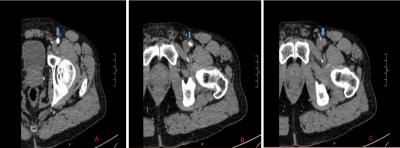

肌钙蛋白I升高至22.4 ng/mL(正常值<0.07 ng/mL)。肌酸激酶(CK)在328 U/L(参考范围55~170 U/L)升高。通过鼻咽拭子进行的冠状病毒检测为阴性。左下肢的计算机断层扫描血管造影(CTA)显示左股动脉急性闭塞,下肢动脉血管细小且显示不佳(图2)。

图2